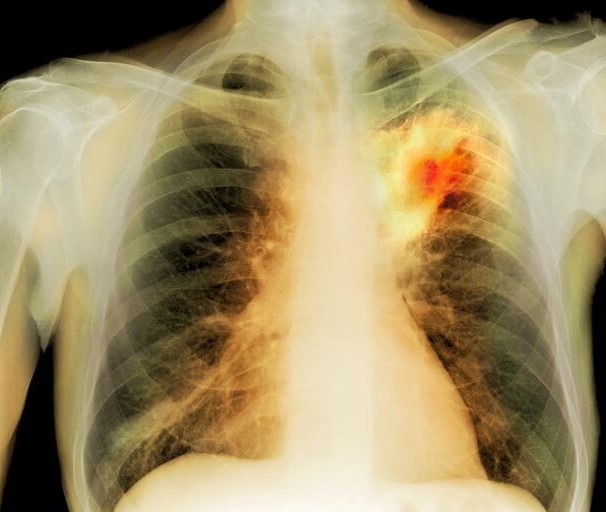

La cavidad del absceso está llena de material purulento y está rodeada por una pared de tejido necrosado. La presencia de esta cavidad en el parénquima pulmonar es lo que se conoce como cavitación, una característica distintiva del absceso pulmonar. Los síntomas típicos incluyen fiebre, tos productiva, dolor torácico y, en algunos casos, expectoración sanguinolenta.

El diagnóstico del absceso pulmonar se realiza mediante la combinación de hallazgos clínicos y pruebas de imágenes, como la tomografía computarizada. El tratamiento implica el uso de antibióticos específicos para combatir la infección bacteriana causante. En algunos casos, puede ser necesario drenar la cavidad purulenta, y esto se puede lograr mediante procedimientos como la punción con aguja guiada por tomografía computarizada o, en situaciones más graves, mediante intervención quirúrgica.